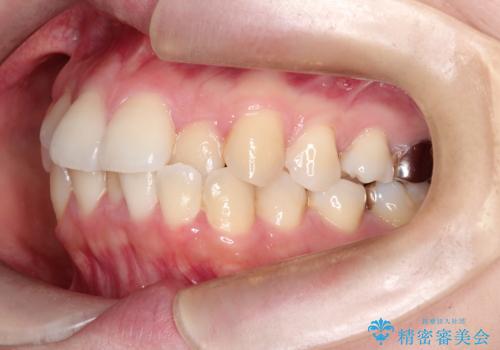

- 主訴:口元を下げて前突感を無くしたい、下の歯の凹凸も無くしたい

右側第二小臼歯、左側第一小臼歯、下顎両側第一大臼歯を抜歯しワイヤ-矯正を行いました。

骨格的顎の変位を認めたため、顔貌に対しピッタリ上下の歯の正中を合わせることは難しいと説明し、上下左右計4本小臼歯を抜歯しワイヤー矯正治療を行いました。